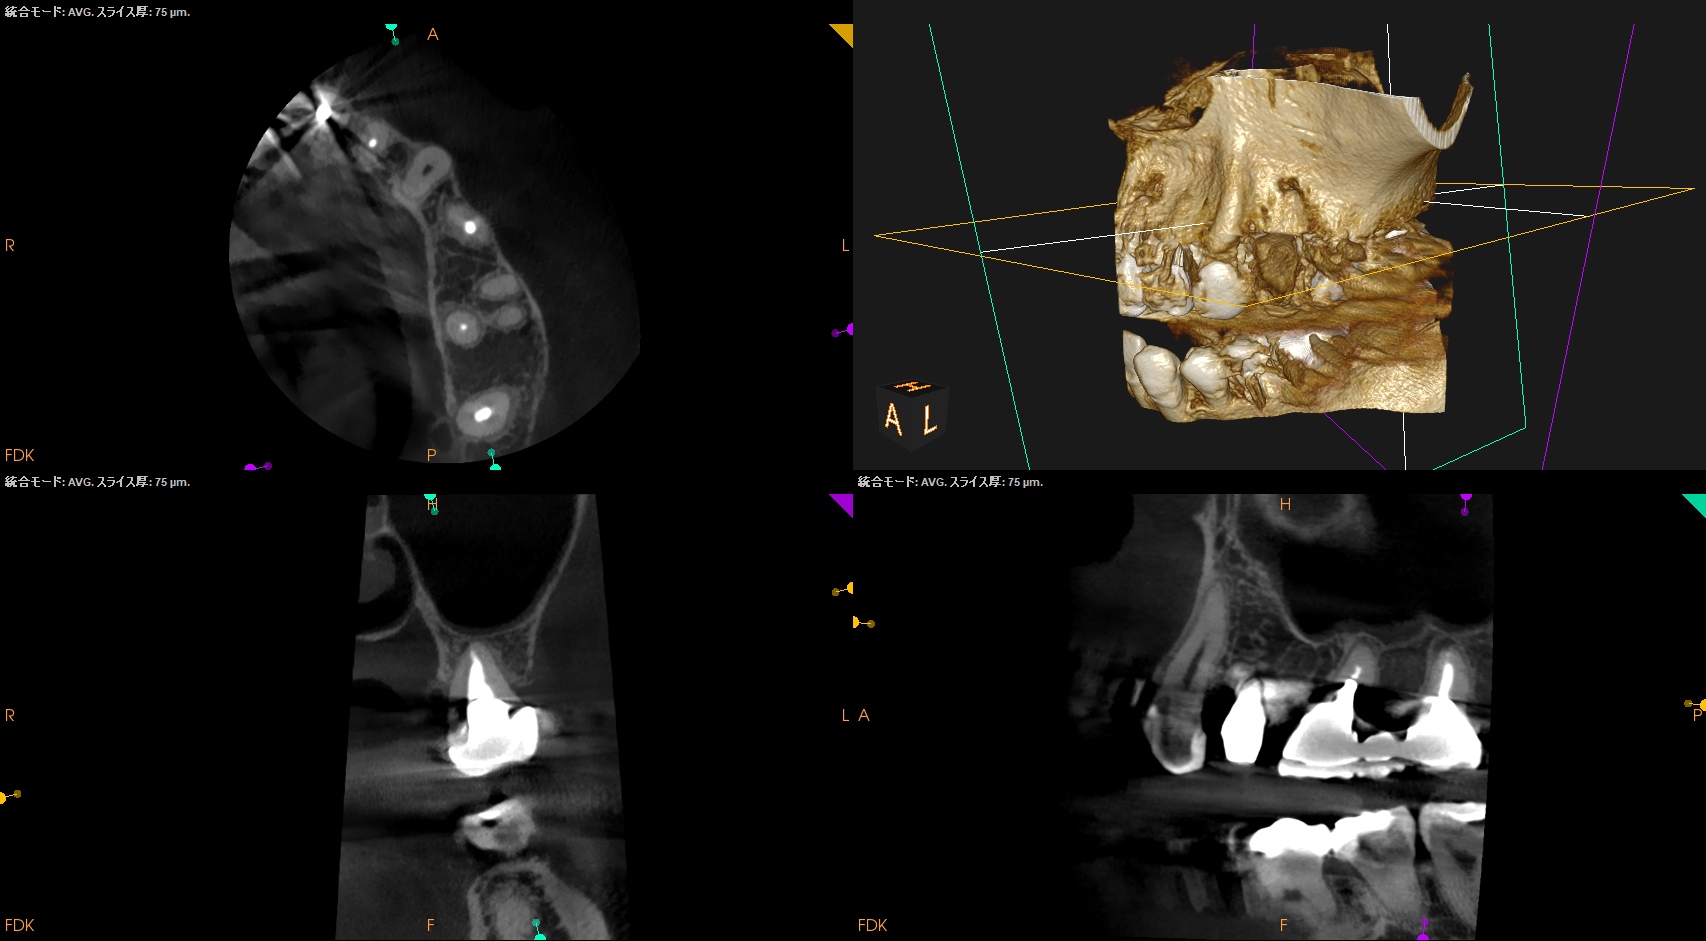

CBCT(2024.7.1)

#3

MB

DB

P

MB,DB,Pと3根全てに病変がある。

しかも形成が不完全だ。

再根管治療が濃厚である。

#14

MB,DBには病変がないが、Pに存在する。

これは頭が痛い。

パラタルフラップも困難なケースだからだ。

#16